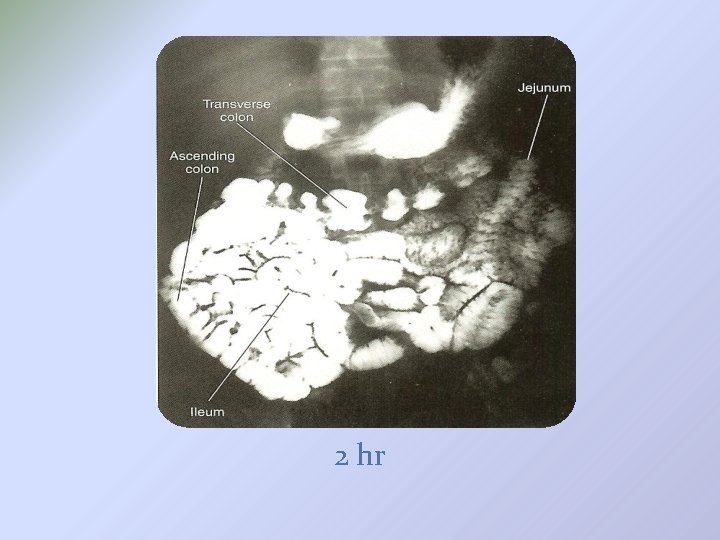

1. Ba Meal Follow through � Routine UGI first � Patient ingests a cup of Ba when UGI series is completed (note the time) � 30 min PA radiograph (30 min after 1 st Ba ingestion, usually 15 min after UGI series is completed) � Half-hour interval radiographs until Ba reaches large bowel (usually 2 hours) � If more time is needed(> 2 hrs) 1 -hour interval radiographs are obtained. � Optional: spot films of ileocecal valve using compression cone? ? To separate the bowel loops that may obscure the terminal ileum

�PA 30 min 1 hr

2 hr